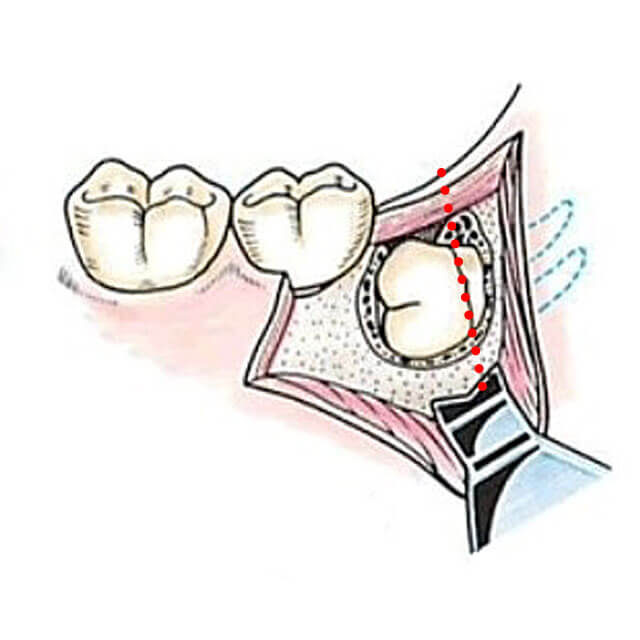

親知らずの抜歯の流れ

1,抜歯部位及びその周囲の消毒をします。

2,抜歯部位周囲に麻酔(浸潤麻酔、場合によっては伝達麻酔も併用)を行います。

3,親知らずの周りの歯ぐきに切開を行います。

4,親知らずの周りの骨を削り、歯の歯冠部分を露出させます。

5,埋伏歯の歯冠をタービンで分割し除去します。

6,残った歯根部分を抜歯します。歯根が2本以上あって大きく曲がっていたり、歯根が肥大していたり、骨と癒着していて、そのままでは抜歯できない場合は歯根を分割したり、歯根周囲の骨を削ったりして抜歯します。

7,抜歯部を生理食塩水にて入念に洗浄します。

8,切開した粘膜を縫い合わせます。骨内の血管からの主家kつが止まりにくい場合や内科治療上の内服薬などで抜歯した部分に止血剤を使用します。

9,縫合した場合は抜歯後約1週間で抜糸します。

イラストの出典「抜歯の臨床」医歯薬出版